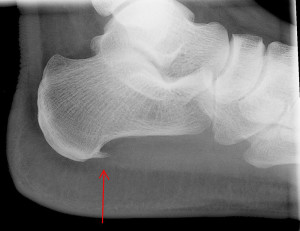

Как правило, недуг мучает представительниц слабого пола, проживающих в городах. Но на самом деле болезнь может настичь кого угодно. Первым симптомом, который является весьма ощутимым, служит резкая боль в пятке при ходьбе. Почему же это происходит? В первую очередь, причиной служит плоскостопие, и риск увеличивается, если оно является продольным, поскольку при нем перераспределяются нагрузки на стопу, в итоге наблюдаются некоторые негативные явления.

Выявить причин, из-за которых произошло костное разрастание, означает подобрать правильное лечение.

Как только ортопед сделает заключение, встает вопрос о том, какая терапия должна быть проведена, чтобы шпора ушла. Народная медицина, скорее всего, в данном случае окажется неуместна и снимет боль лишь на время. Более того, заболевание может даже усугубиться. Произвести эффективный курс лечения можно лишь при содействии умелого специалиста. Тип лечения может быть консервативным и оперативным.

Лазерное удаление шпоры

Лазерная терапия не устраняет саму шпору, но излечивает воспаленные ткани в этой области. Однако лазер может относиться и к хирургическим методам, который представляет собой дробление шпоры.

Данная операция требуется в случае, если другие методы лечения не принесли успеха. Проводятся такие операции при помощи современных технологий, пациенты переносят их легко. Перед тем, как работать с лазером, производится перфорация пяточной шпоры с использованием иглы, при помощи которой производится внутрикостная анестезия.

Методика дробления позволяет удалить лишь кальциевый нарост, причины возникновения он не устранит. Потому не исключены рецидивы. Причины болезни устраняются самим пациентом, при таких условиях можно говорить об эффективности лечения шпоры.